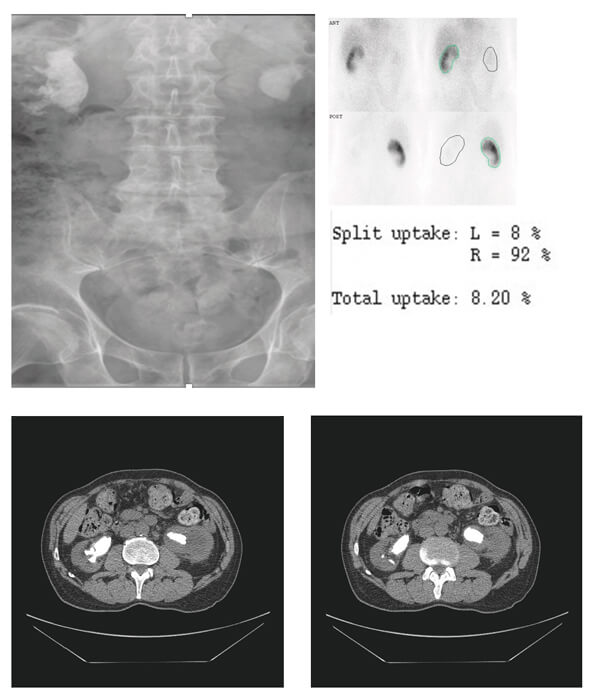

- What do the X-ray KUB and the CT scan images show?

- What do these images show, and which kidney should you treat first?

Bilateral large / staghorn renal calculi.

BOSE - the stones in the Best functioning kidney should be treated first. If function is equal, treat the Obstructed kidney, if neither obstructed treat the Symptomatic side, and if all else is equal treat the Easiest side first! A Technetium-99m (Tc99) labelled dimercaptosuccinic acid (DMSA) renal scan should be done to define differential renal function. A mercapto-acetyl-tri-glycine (MAG3) scan is an alternative but less reliable in this context. Assessment of overall renal function with eGFR/U+E would also be recommended, as well as a mid-stream urine sample.

This is a DMSA scan showing a significantly reduced contribution from the left kidney (8% compared to 92% on the right). The right kidney should be treated first.